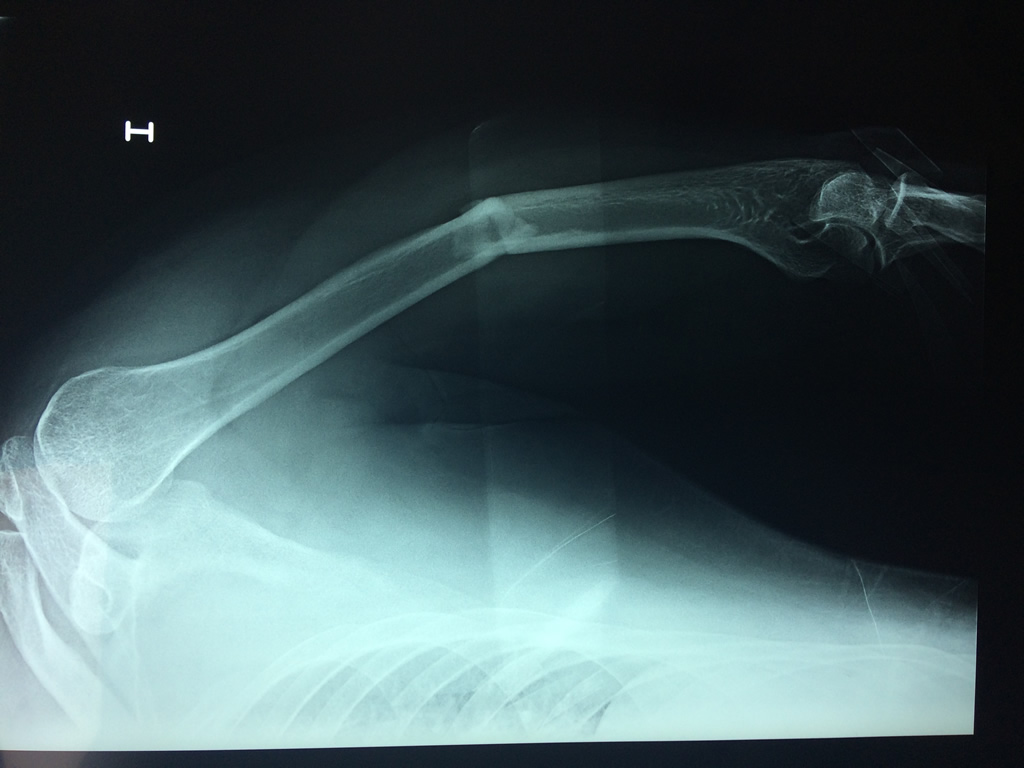

Cirugías de Hombros - Húmero

El Húmero (en latín, humerus) es el hueso más largo de las extremidades superiores en el ser humano. Forma parte del esqueleto apendicular superior y está ubicado en la región del brazo. ... El extremo proximal del húmero tiene la cabeza, cuellos quirúrgico y anatómico y tubérculos mayor y menor.